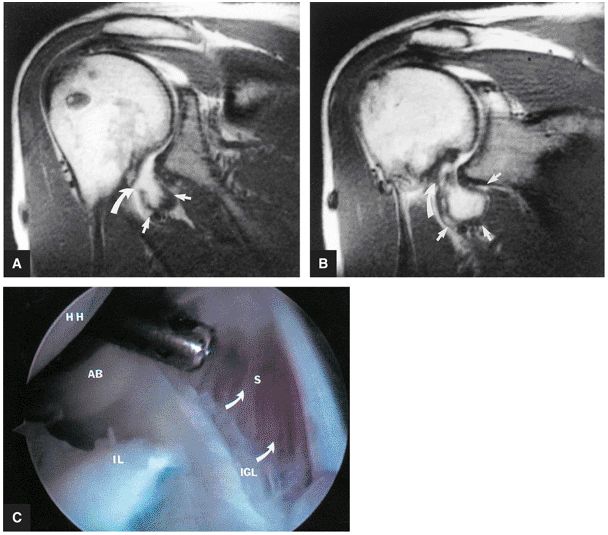

FIGURE 8.80 ● (A) The axillary pouch of the IGHL is seen on a T1-weighted sagittal MR arthrogram. Arrows and ap, axillary pouch of IGHL; b, biceps tendon; s, supraspinatus tendon; sub, subscapularis tendon. (B) The IGHL complex. An arthroscopic photograph shows the anterior band (AB) and axillary pouch (AP) components of the inferior glenohumeral ligament (IGL) complex. The inferior pole of the glenoid (IP) and the anatomic neck attachments of the IGL complex (AN) are shown as viewed from the axillary pouch. HH, humeral head.

|

FIGURE 8.81 ● (A) The anterior band (ab) and posterior band (pb) of the IGHL (curved arrows) extend from the glenoid origin to the humeral attachment, as seen on an enhanced T1-weighted sagittal (oblique) image. C, coracoid; H, humeral head. (B) On a gross shoulder specimen, the superior course of the anterior band (AB) of the IGHL is identified (triangular marker). The glenoid (G) and humeral head (HH) are also identified.

FIGURE 8.82 ● A gross shoulder specimen illustrates the structure of the inferior glenohumeral ligament (IGL) complex. With abduction of the humerus, the IGL structures are more prominent and taut in position. Coronal oblique MR images routinely show the lax axillary pouch of the IGL when the humerus is in the adducted position. Curved arrow, axillary pouch; AB, anterior band; AL, anterior labrum; HH, humeral head; PB, posterior band; PL, posterior labrum.